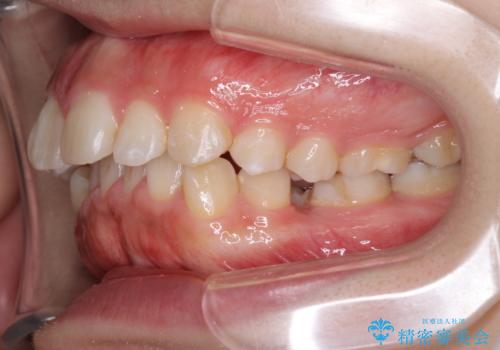

- 歯並びがガタガタなのと、口が閉じずらいのを主訴に来院されました。

上下左右の歯を1本ずつ、合計4本抜歯して、ワイヤー矯正を行うこととなりました。

右上の歯は、歯並び的には前から4番目の歯を抜歯したかったのですが、5番目の歯がすでに治療してある歯でしたのでこちらの歯を抜歯しました。

これにより少し治療期間が延びてしまいましたが、健康な歯を残すことができました。